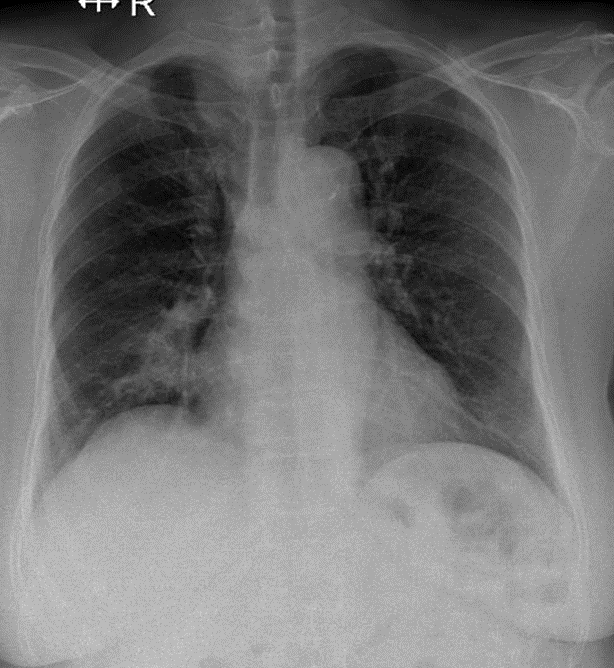

1-Thâm nhiểm phế nang thùy giữa phổi (P) => Viêm phổi 2-Cung động mạch chủ đóng vôi